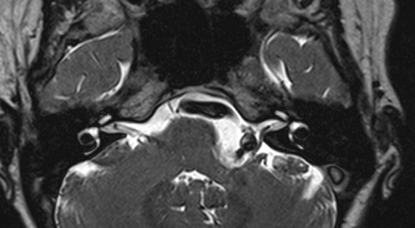

Επιδερμοειδής όγκος οπίσθιου βόθρου, σε γυναίκα 46 ετών, στην οποία προκαλούσε αφόρητο πόνο κεφαλής και προσώπου